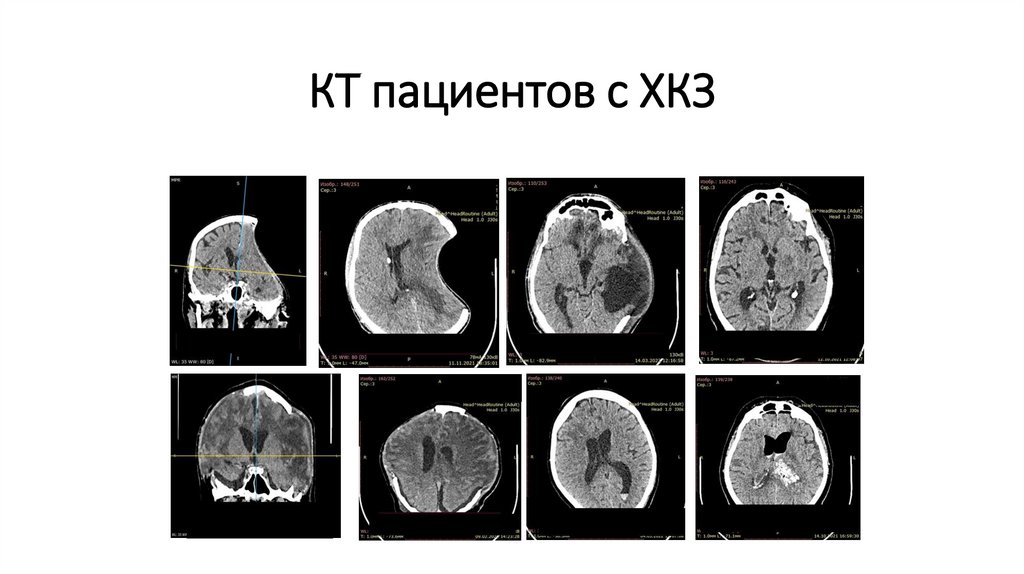

КТ пациентов с ХКЗ

62. КТ пациентов с ХКЗ